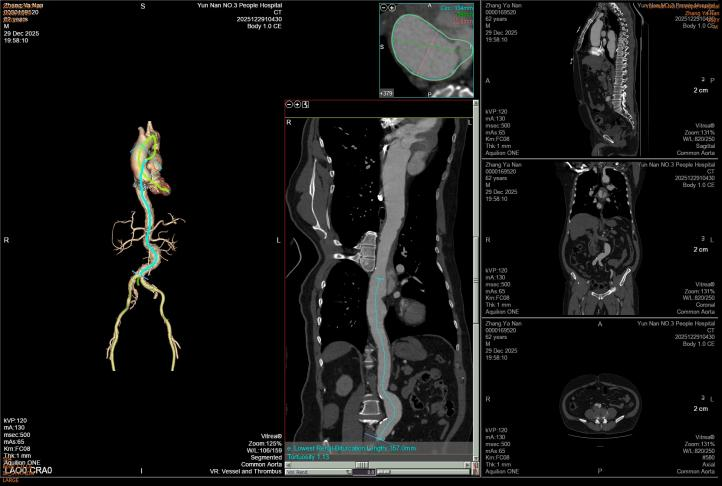

第二例患者诊断为胸腹主动脉夹层(Debakey Ⅲ型,逆向撕裂至主动脉弓部)。治疗团队先行采取非手术方案促进血肿吸收,再限期行腔内修复术。术中运用院内新技术“支架体外开窗”,成功保留了左侧锁骨下动脉血供;同时,腹主动脉覆膜支架采用术中自制微孔设计,在实现真腔扩大的同时,进一步减少了对脊髓血供的影响。

第二例患者术前CT